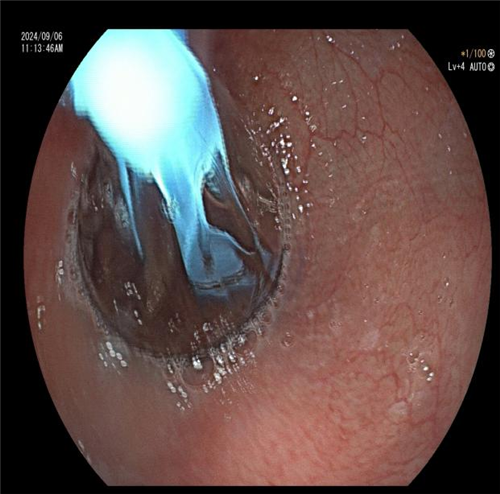

食管钡剂造影显示不同程度的食管扩张(钡剂潴留)以及食管下端变窄呈「鸟嘴样」改变,这是贲门失弛缓症的重要诊断依据。曾主任与患者及家属充分沟通后,决定为其施行 “内镜下贲门大球囊扩张” 治疗。该治疗的基本原理是将气囊置入食管内,再向气囊内注入气体,使其扩张到一定程度,使 LES 的肌纤维断裂,从而达到松弛 LES 的效果。术后,患者恢复良好。